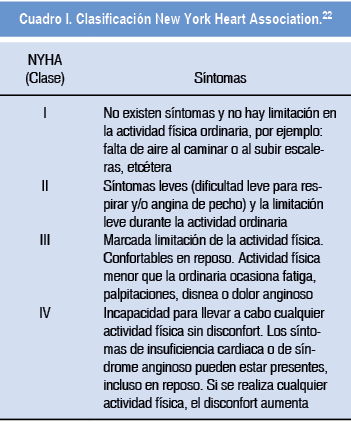

Los aspectos importantes a evaluar en pacientes embarazadas con este defecto y que determinarán la evolución clínica son: detectar presencia de arritmias atriales, grado de hipertensión arterial pulmonar, presencia de enfermedad vascular pulmonar obstructiva que se desarrolla por el sobreflujo a la circulación pulmonar condicionada por el corto de izquierda a derecha, presencia de embolismo paroxístico ya que el embarazo condiciona un estado hipercoagulable y puede incrementarse la frecuencia de estos eventos y presencia de insuficiencia del ventrículo derecho (Figuras 2 y 3).